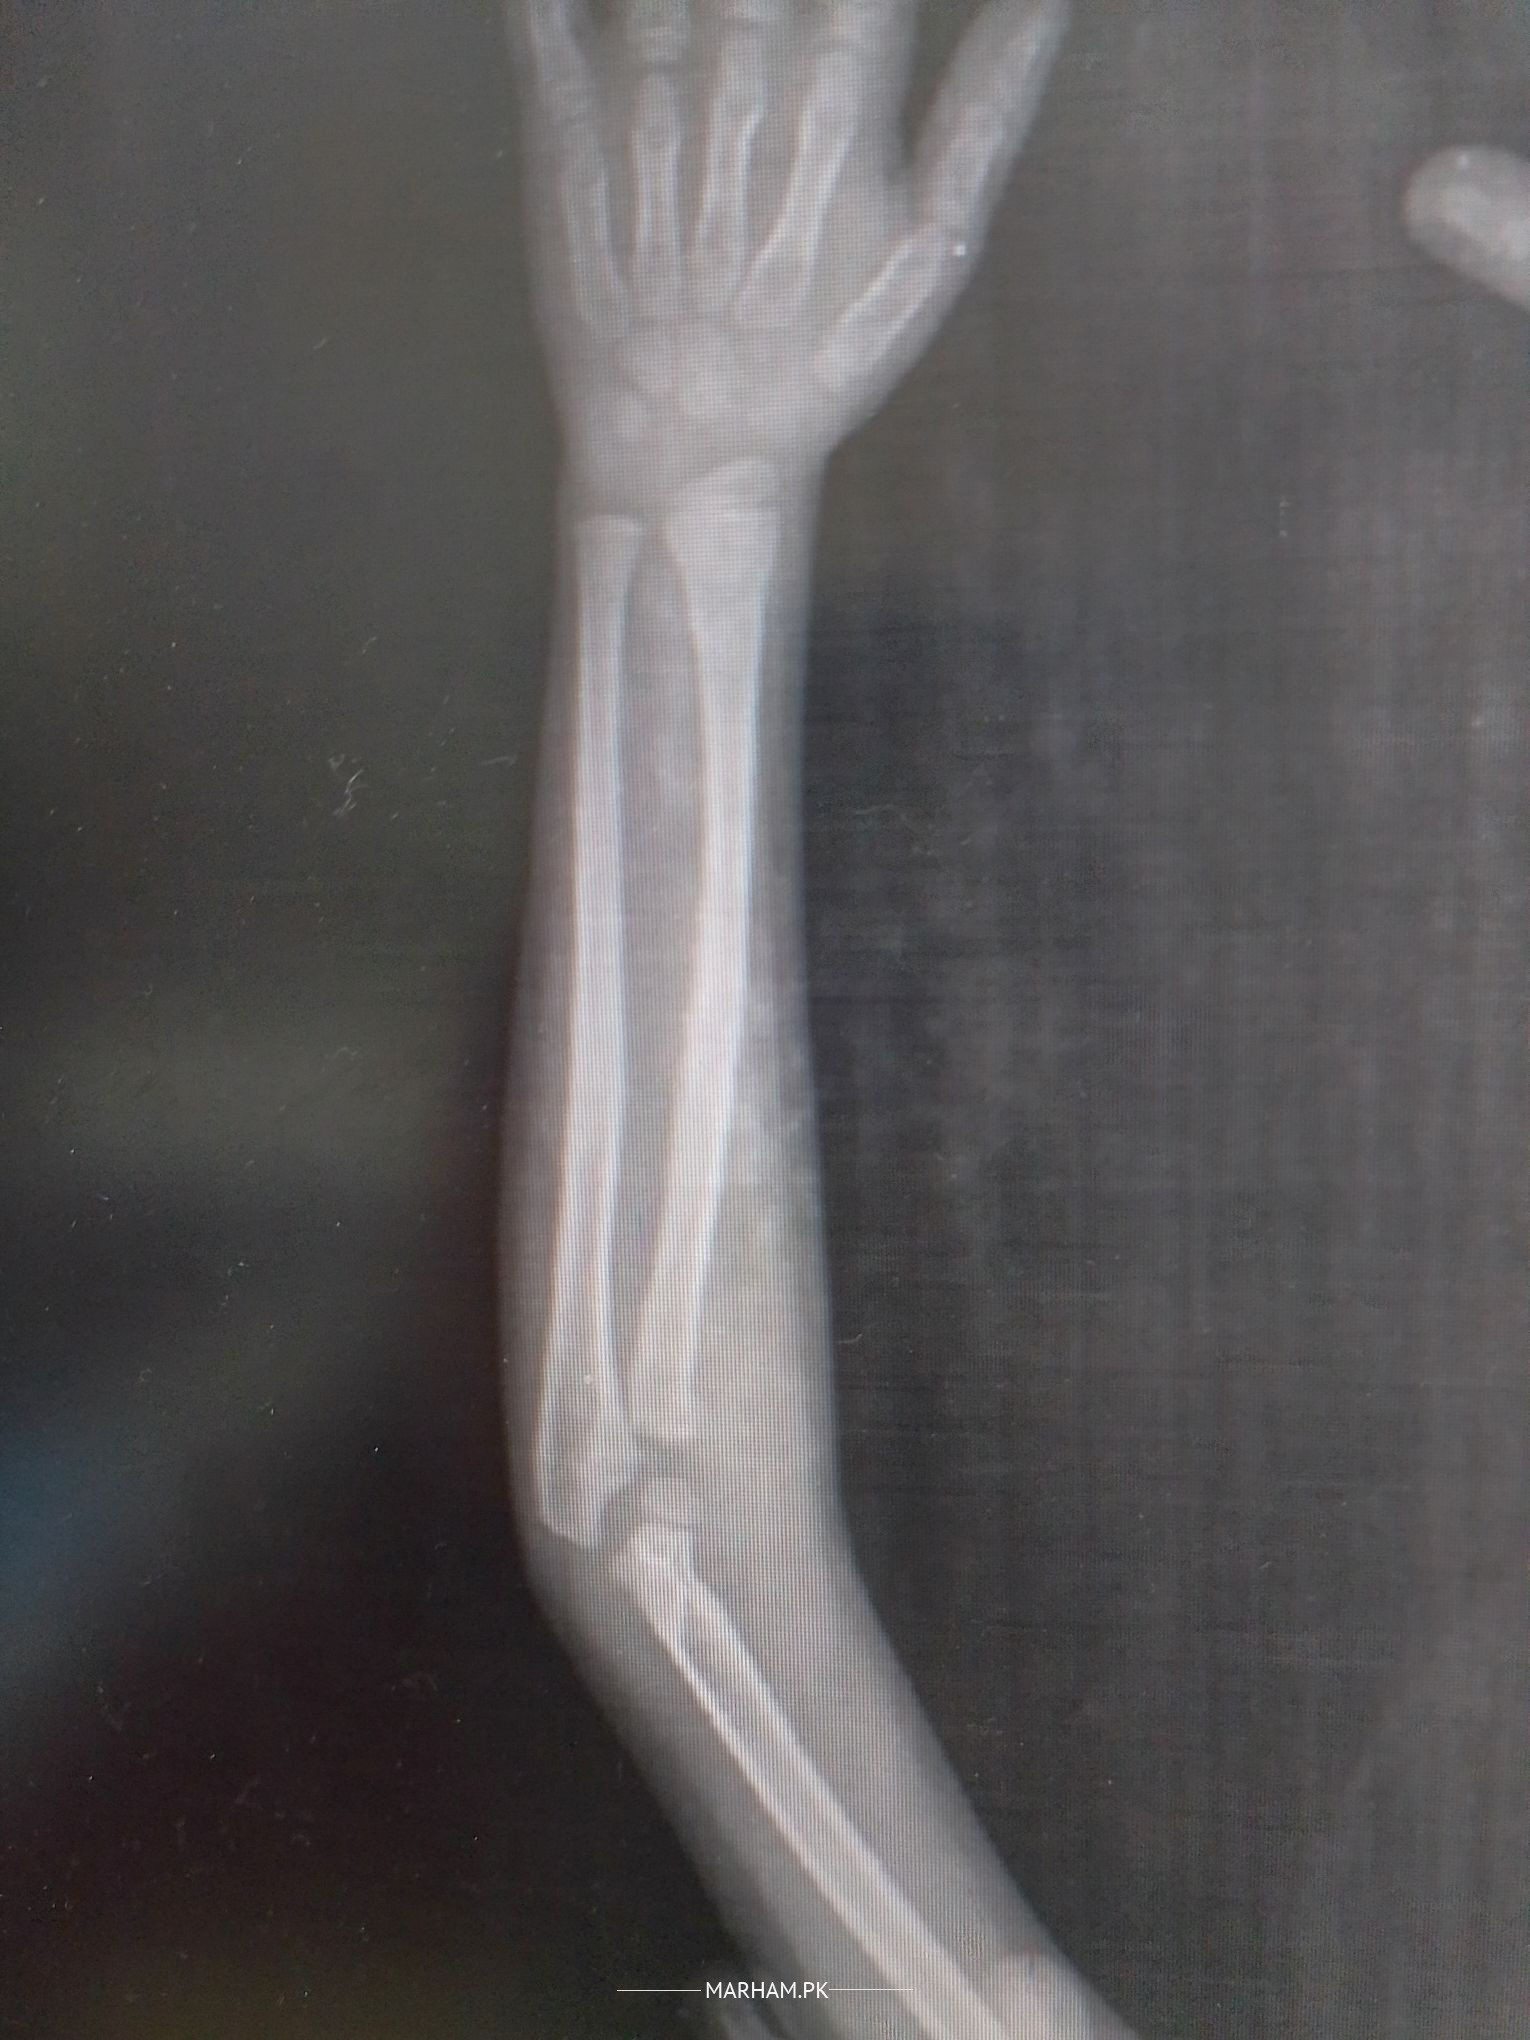

x-ray shows doubtful fracture of Head of radius

For Treatment History and Examination is important.On xrays radius (bone on outer side)is short and head seems to be fractured.

most likely treated by jarrah.

fracture hai head of radius but operation ki zrurat ni hai. 1 week plaster and then start moving elbow takay stiffness na aaiy.